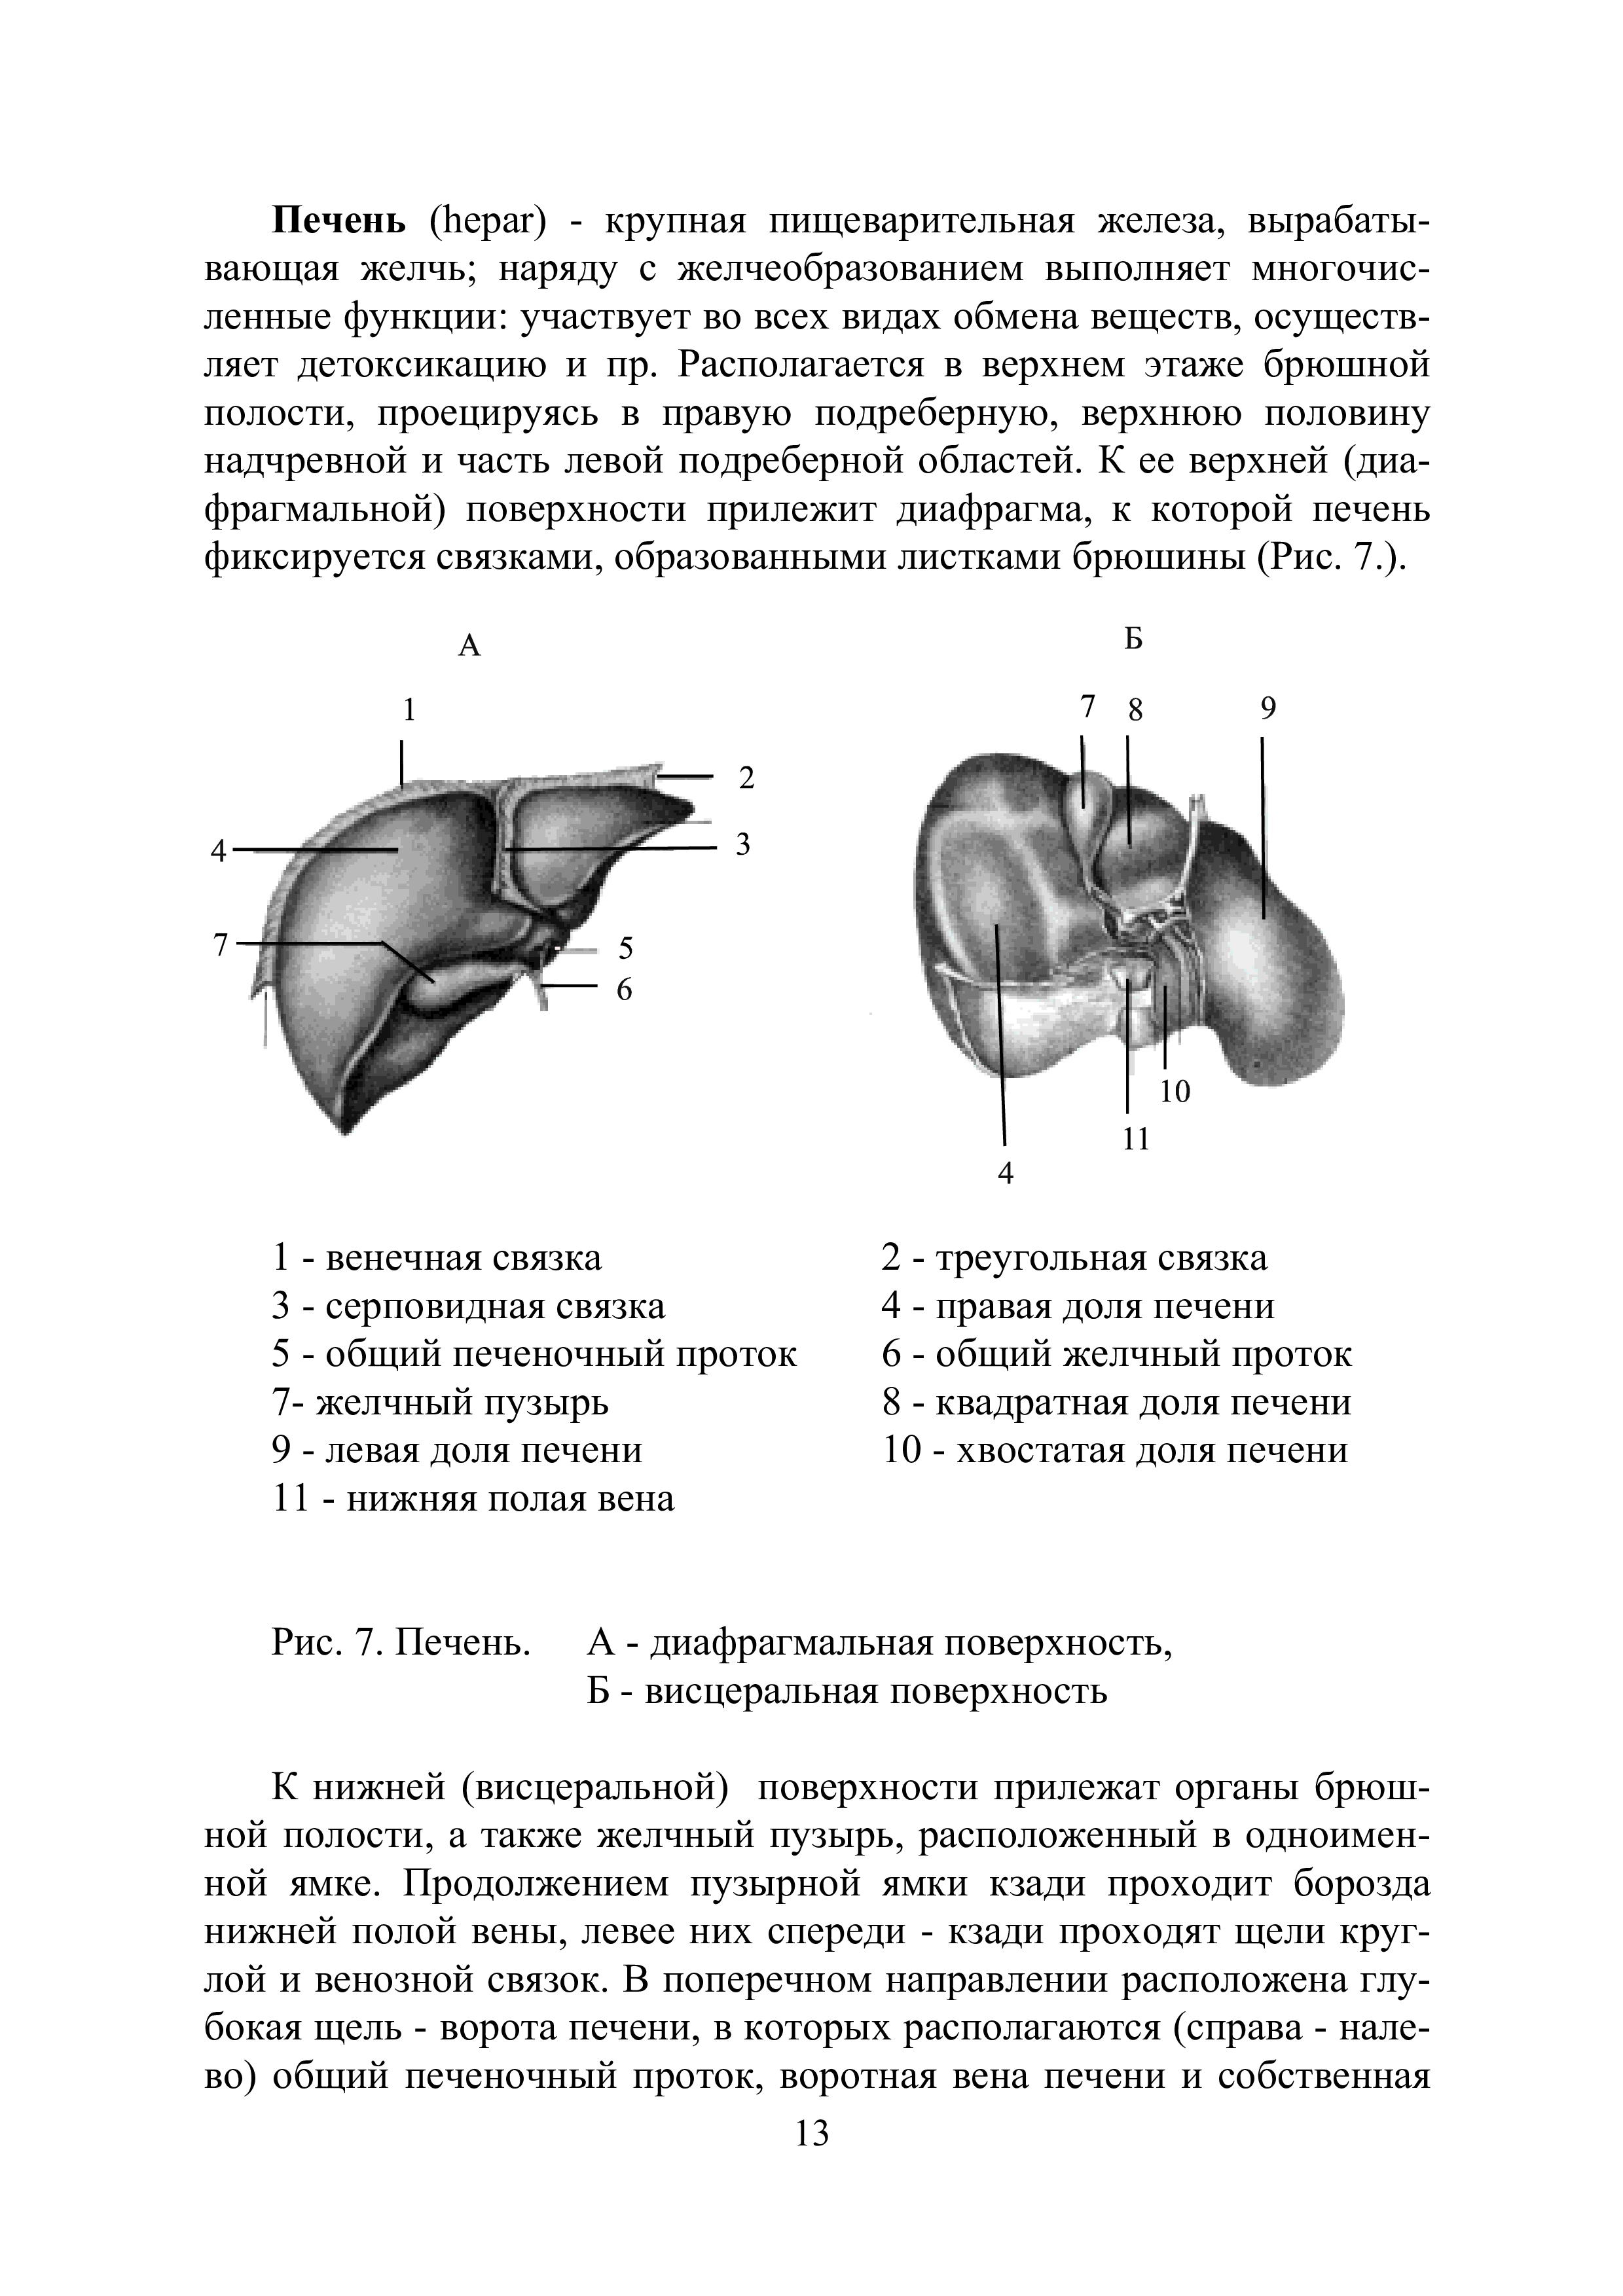

"Анатомия человека. Часть 3. Спланхнология: Методические указания" - читать интересную книгу автора (Полякова-Семенова Н.Д., Мещерякова М.Ю.,...)